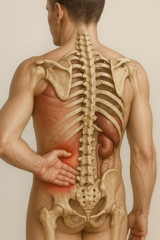

Anatomi och påverkan på nerver

L5-nivån i ryggraden är en kritisk punkt där mycket av kroppens vikt bärs. Denna nivå, som är den femte ländkotan, är belägen längst ner i ländryggen och är en del av den lumbosakrala övergången. Ett diskbråck vid L5 kan påverka nervrötterna i området, främst ischiasnerven, vilket leder till de typiska symptomen av smärta och domningar i benen.

För att bättre förstå hur ett diskbråck påverkar nerverna kan visuella element som diagram och illustrationer vara till hjälp. Dessa kan tydliggöra hur bråcket trycker på nervrötterna och orsakar de symptom som många upplever.